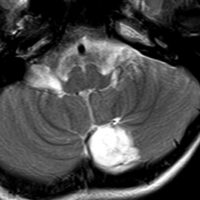

小脳類皮のう胞

偶然発見された女の子のものです。左のCTで石灰化があります。右の拡散強調画像 DWI で白く高信号に描出されるのが特徴です。手術では腫瘍内部に毛髪がたくさんありました。後下小脳動脈に強く癒着していて,脳軟膜からの剥離もできませんでしたが,完全摘出しました。無症状でも”完全”摘出 complete removal するべきです。